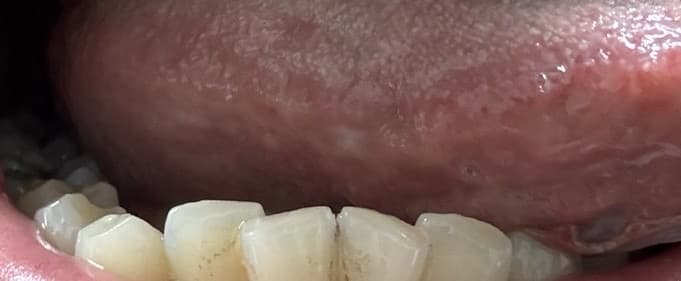

일어나서 확인해보니 첫번째 사진처럼 되어있더라구요

저번주 금요일에 자고일어났더니 혀에 뭐가 났는데요

저번주 금요일에 자다가 혀에 통증이생겼는데

깨문건지 모르겠는데 엄청 건조했어요 입안이